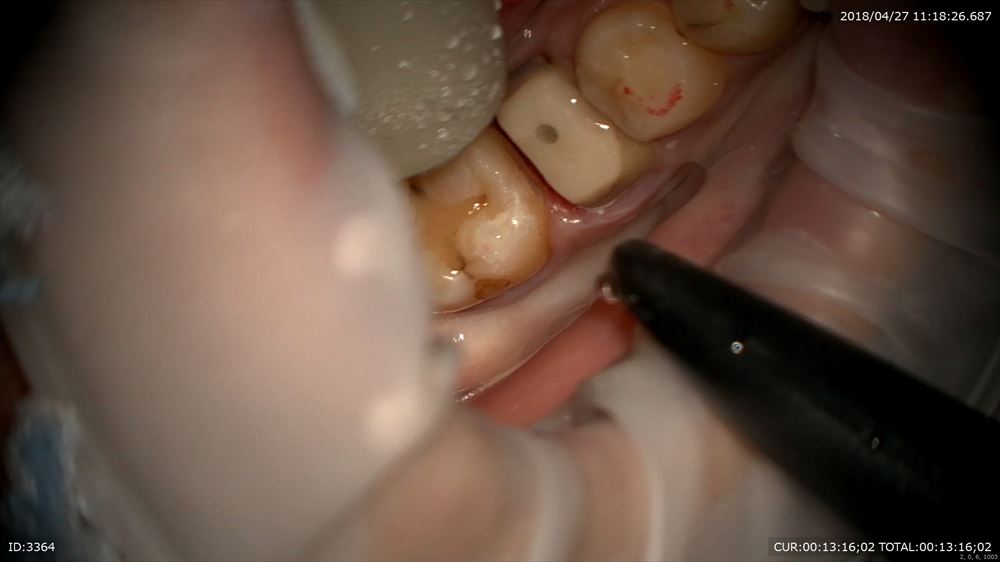

私が自らデブライドメントを行うのは下記のような虫歯やクラックを見つけその方の情報をここでも採取しているから。

虫歯見つけた!!